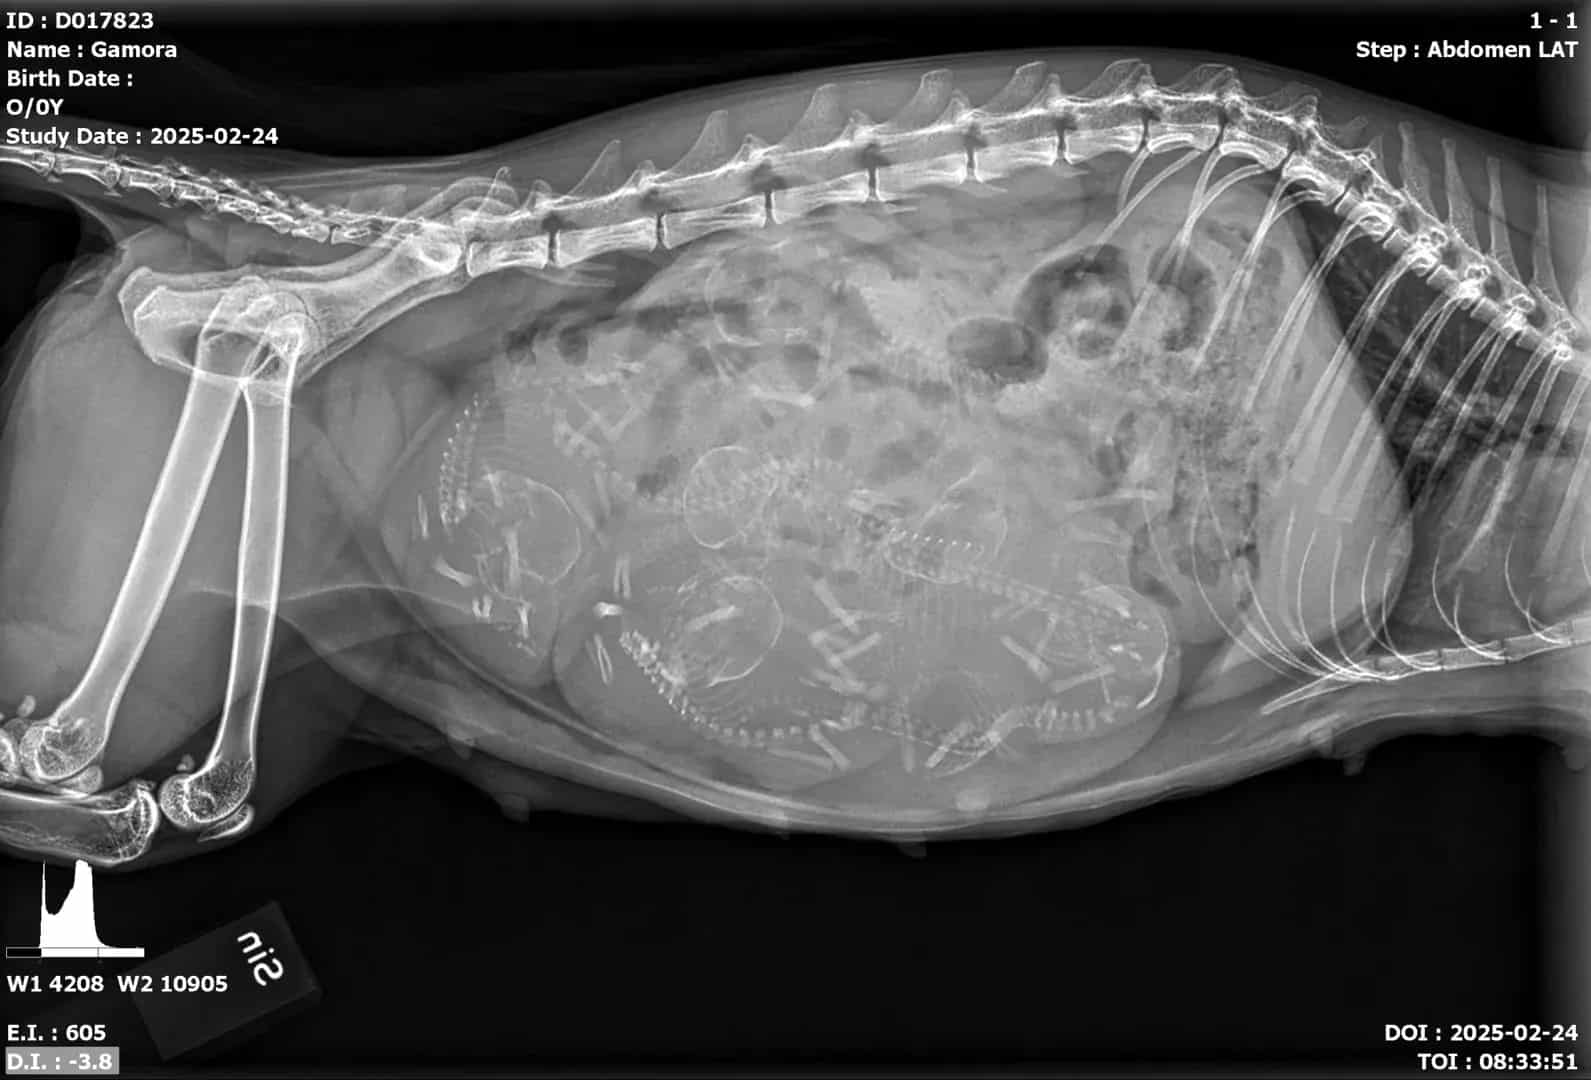

Följ Gamoras resa genom graviditeten och förberedelserna inför hennes fjärde kull kattungar i mars.

Gamora väntar sin 4’e kull här i början av Mars månad